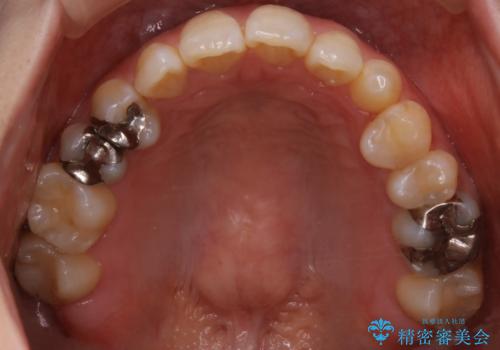

- 受け口で、前歯の嚙み合わせが気になるとの事でご相談にいらした方です。先天的に右上犬歯がなく、左上犬歯も小さい状態でした。矯正治療にて周囲の歯を動かして歯のスペースを確保した上で、被せものにて歯を作っていきました。

歯科技工士さんの熟練した技術により、周囲の歯としっかりなじむ天然歯のような被せ物をお作りすることが出来ました。

矯正治療と補綴治療をうまく組み合わせることで、美しい口元に仕上げることが出来ました。矯正治療、補綴治療をまとめて行える総合歯科治療を体現した治療といえます。